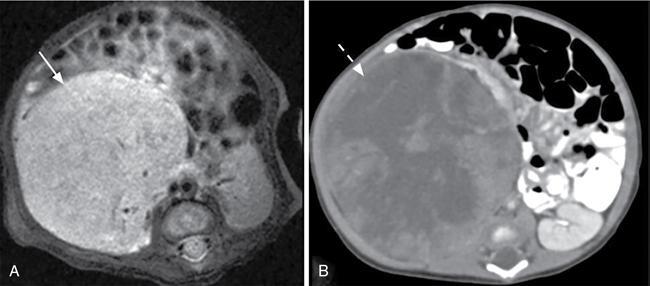

Naren Hemachandran, Devasenathipathy Kandasamy, Geetika Khanna Renal neoplasms are rare in children, accounting for less than 10% of childhood cancers. Nonneoplastic conditions like hydronephrosis, hypertrophied column of Bertin, foetal lobulations, calyceal diverticulum, simple renal cyst and infective causes like acute pyelonephritis, renal abscess can present as a renal mass clinically or on imaging. These nonneoplastic conditions are more common than true neoplasms in the early infantile period and radiologists should be aware of these conditions to avoid misdiagnosing them as neoplasms. In this chapter, we describe a clinic-radiological algorithmic approach as well as review the common paediatric renal neoplasms. Renal neoplasms can present as abdominal distension, mass palpable per abdomen (commonly detected by parents while bathing a child), flank pain, haematuria or rarely with other atypical symptoms. Imaging plays an important role in the detection, characterization, preoperative staging, image guided sampling, treatment planning and posttreatment follow-up or surveillance. Ultrasonography is the initial modality for detection as well as characterizing a mass as solid or cystic. This differentiation plays an important role in characterizing renal masses in children as further elaborated in this chapter. Computed Tomography (CT) is the preferred modality for further evaluation due to high spatial and temporal resolution and short scan times. In addition, CT allows for simultaneous evaluation for lung metastasis, a critical part of staging. Due to the need of sedation or general anaesthesia because of the longer acquisition time, Magnetic Resonance Imaging (MRI) is primarily used as a problem-solving tool and for evaluation of bilateral renal neoplasms. The characterization of renal masses in children may not always be possible by imaging due to significant overlap in the imaging and clinical features. In this chapter, we propose a radiological algorithm for the characterization of various renal masses in children. This is based on the primary nature of the mass and they are classified into predominantly fat containing, predominantly cystic and predominantly solid groups (Fig. 10.9.1). Predominantly solid masses are further subclassified based on the age at presentation. Various neoplasms have been categorized into these groups based on the most typical findings. This radiological algorithm is not absolute but intends to provide a practical approach to narrow down the differential diagnosis in a child with a renal mass. Angiomyolipoma is the most common fat-containing renal neoplasm in children. Other lesions like renal cell carcinoma, Wilms’ tumour also can show fat within. However, in such cases, fat component is seen along with other solid/cystic components and these do not present as predominantly fat containing and hence are described elsewhere. Angiomyolipomas are benign neoplasms and are composed of varying amounts of dysmorphic blood vessels, smooth muscle and fatty elements. In the adult population, the majority of them are sporadic, while the remaining 20% are seen in association with tuberous sclerosis. However, in children, the majority of the detected lesions are seen in association with tuberous sclerosis. The presentation varies with the size of the lesion. Small angiomyolipomas are typically detected during screening/annual surveillance of children with tuberous sclerosis. Those more than 4 cm are more likely to undergo spontaneous haemorrhage and present with pain, haematuria or rarely with life-threatening retroperitoneal or subcapsular haemorrhage. Although they are benign neoplasms, rarely they can show extension into the renal vein and subsequently into the inferior vena cava. On imaging, identification of a predominantly fat-containing mass enables us to confidently diagnose an angiomyolipoma (Fig. 10.9.2). However, there can be significant variation in the amount of fat within the lesion and some authors classify them into fat rich and fat poor angiomyolipomas. The fat can be either macroscopic fat or microscopic fat. The imaging features vary depending on the fat content. On ultrasonography, they are usually hyperechoic. The degree of heterogeneity of the lesion and the vascularity increases with increase in size of the lesion. Intratumoural prominent vessels, vascular lakes and pseudoaneurysms are well demonstrated on colour Doppler. CT is very helpful for the detection of the macroscopic fat even in smaller lesions. MRI helps in the demonstration of microscopic fat using chemical shift imaging, in which microscopic fat shows typical drop in signal intensity in opposed-phase images compared to in-phase images. Dixon technique is also very well suited for detection of small fat-containing angiomyolipomas, as the small foci of fat are very conspicuous on fat only images. The most common lesions that show predominant cystic areas on imaging are multilocular cystic nephroma, cystic partially differentiated nephroblastoma (CPDN)/cystic Wilms’ tumour. Previously these three tumours were considered to be along the same continuum with increasing blastemal components in CPDN compared to cystic nephroma, though recent studies have shown that these are distinct clinical/pathological entities. Multilocular cystic nephroma is a benign neoplasm more commonly seen in young boys. On sonography it appears as multiloculated cystic lesions with multiple thin septae within. The walls of the cyst and the septae show smooth thin enhancement on postcontrast imaging with no nodular or solid enhancing areas. The microcystic type can artifactually appear solid on imaging. These tumours typically present as Bosniak 3, and less commonly as Bosniak 2 renal cysts. Herniation into the collecting system is a characteristic finding, although it is not always seen (Fig. 10.9.3). Recent studies have shown a strong association of multilocular cystic nephroma with DICER-1 mutation. The lungs should be evaluated in these children for associated cystic lesions which can represent pleuropulmonary blastomas. The presence of solid enhancing component within a predominantly cystic lesion or nodular enhancement along the septae of a cystic lesion point towards a diagnosis of cystic Wilms’ tumour. Clinical, demographic features and the response to chemotherapeutic agents are similar to that of Wilms’ tumour, which is considered in detail in the next section. Most of the renal neoplasms in children are predominantly solid with significant overlap of imaging and clinical features. There are some typical features which are however, not seen always. We have further divided the predominantly solid masses based on the mean age of presentation of the lesions. This approach is not infallible, due to the wide range of the age of presentation of these lesions, and only aims to provide a practical working algorithm. Many times, even after the best of the efforts, it is impossible to pinpoint to a specific diagnosis and histopathology is needed to make the final diagnosis. Mesoblastic nephroma is the most common solid renal tumour in neonates. It was originally thought to represent congenital Wilms’ tumour. However, Bolande et al. in the late 1960s first described it as a separate entity and since then has been recognized as a distinct entity. It is also called as foetal renal hamartoma or leiomyomatous hamartoma. Mesoblastic nephroma typically presents in the first few months of life though it may be detected in utero on routine antenatal ultrasound or MRI studies. It shows a male preponderance. There are two histologic subtypes – classical and cellular types. The classical type shows features similar to that of uterine leiomyoma and is homogeneous with a whorled appearance. The cellular type tends to be larger, crosses the midline more often and occurs in slightly older patients (>3 months of age). Both the subtypes are unencapsulated but the cellular subtype shows a ‘pushing’ border with the adjacent kidney. The cellular type shows a multiseptated appearance with haemorrhage, necrosis and cystic areas resulting in a heterogeneous appearance (Fig. 10.9.4). Cellular mesoblastic nephroma tends to be more aggressive than classic. Calcification is rare and the absence of calcification is an important finding to differentiate it from the other common lesions seen in infants.